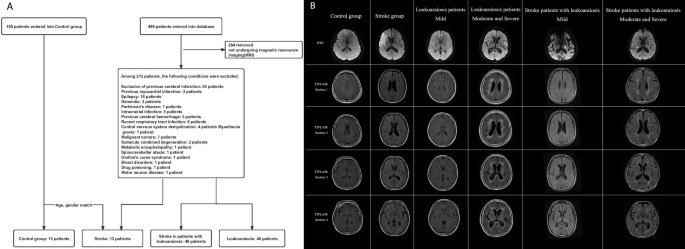

A total of 499 patients were enrolled into the database for patients with leukoaraiosis and stroke in leukoaraiosis patients. We selected individuals admitted to Sanming First Hospital Affiliated with Fujian Medical University in China from 2021 to 2022. Patients with severe heart, lung, liver, or kidney diseases; central nervous system tumors; and acute cerebral hemorrhage were specifically excluded. The stroke patients were an acute ischemic stroke patient (onset within 48 h), and they were required to demonstrate no, mild, or severe subcortical white-matter changes on cranial magnetic resonance imaging (MRI), and to have no hyperlipidemia or any other conditions that could potentially influence lipid metabolism (Fig. 1A). After applying exclusion criteria, a total of 215 consecutive neurology outpatients and inpatients were included in the study and underwent clinical brain MRI. To create comparable groups and reduce confounding factors, using “matchIt” package of R language, propensity score matching for sex and age was utilized to result in two distinct groups: the leukoaraiosis patients (n = 40) and the stroke in patients with leukoaraiosis (n = 48). A separate control cohort of 100 individuals was also included in the study. The control group was matched with the stroke group based on sex, age, systolic blood pressure (SBP), diastolic blood pressure (DBP), glucose levels (GLU), and hemoglobin A1c (HBA1c), resulting in two groups of 13 control individuals and 13 matched stroke patients (Table S1). This retrospective research trial was approved by the Fujian Sanming Hospital ethical committee and registered, and all participants provided written informed consent. The study complied with the principles of the Declaration of Helsinki. Our study was approved by the Ethics Committee of the Sanming First Hospital Affiliated with Fujian Medical University (Ethics Approval Number: 2022–44).

We enrolled 499 patients in the database of SanMing First Hospital from 2020 to 2022. Of these, 284 patients were excluded because they did not undergo magnetic resonance imaging (MRI). Among the remaining 215, 99 were further excluded due to medical conditions (Fig. 1A). After propensity matching of sex and age, 40 patients with leukoaraiosis and 48 stroke patients with leukoaraiosis remained for further analysis. The demographics and clinical characteristics of these two groups were summarized in Table 1. Compared to the leukoaraiosis patients, the stroke patients with leukoaraiosis exhibited significant increases in SBP, DBP, GLU, and HBA1c, along with a significant decrease in Fazekas score.

The Fazekas score is a widely used method for visual rating of hyperintense white matter signal abnormalities (WMSA) in magnetic resonance imaging (MRI) data23,24,25. This scoring system serves as a widely utilized means for gauging the extent of white matter hyperintensity pathologies. The Fazekas score spans a range from 0 to 6, wherein a progressively higher score is indicative of an increasingly severe degree of white matter aberrations25. High Fazekas white matter signal indicates moderate to severe white matter abnormalities (i.e. confluent WMSA, Fazekas score of 4–6), while low Fazekas white matter signal indicates mild white matter abnormalities (i.e. absence or punctate WMSA, Fazekas score of 0–3)26. Based on the Fazekas score26, patients in the leukoaraiosis patients and stroke patients with leukoaraiosis were divided into two subgroups (Fig. 1B and Supplementary Table 1).